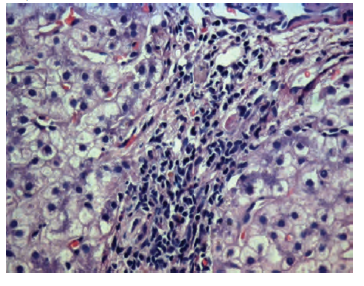

Figure 2. Acute Cellular Rejection

Table 2 presents the histologic diagnoses of 29 liver biopsies obtained > 3 months after transplant during the 5.5-year study period (2011-2017). Most patients were treated with a triple therapy, and only 3.6% (1/28) received monotherapy. One patient with severe rejection had autoimmune hepatitis overlapping with primary biliary cirrhosis. The patient was refractory to methylprednisolone. Simultaneously with the rejection, the patient developed end-stage renal failure. A second incident of severe acute cellular rejection developed in a patient with recurrent HBV infection. The patients with rejection activity index of 3 or 4 did not receive pulse therapy (methylprednisolone) because they had biliary and septic complications. One patient with severe rejection (rejection activity index of 8) stopped immunosuppressive therapy for 1.5 months at 1.5 years after liver transplant. He had cirrhosis due to HBV and HDV and biliary stricture 6 months after liver transplant (Figure 2, A and B).